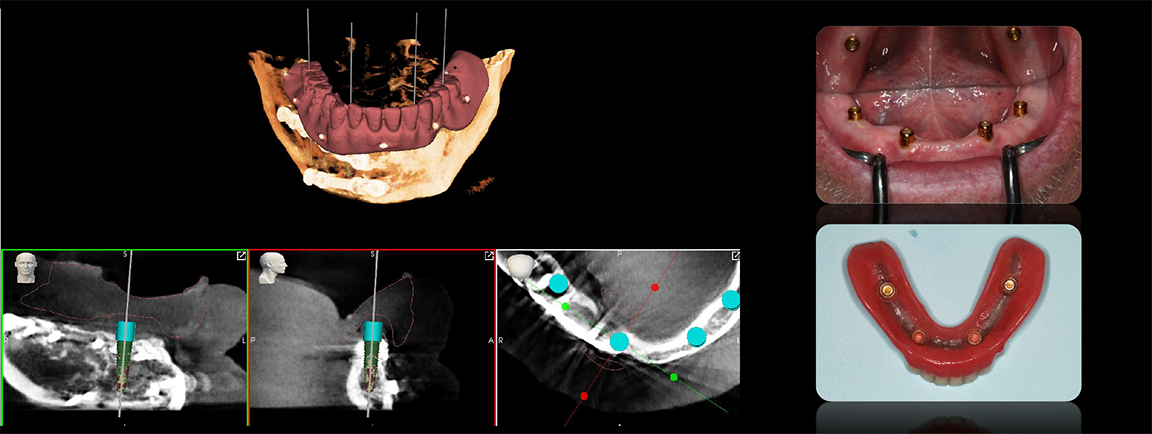

In the case of an edentulous patient, in the virtual surgical planning realm practitioners typically overlay computed tomography (CT) scans for treatment planning purposes and can do so in multiple software platforms (Figure 6). Robotic technology has the same capability to track radiopaque markers, such as gutta percha or global composite.12

The dots between the arches on a CT scan are reference points that are valuable in treatment planning to coordinate data and visualize results to form a blueprint to use in laying the foundation and finding an anatomically correct location for implants (Figure 7). The result is a concerted plan that ends with good results in a predictable manner because the technology allows the practitioner to see everything during planning and surgery. It is not complicated, can happen in the same day, does not involve a protracted treatment planning process, and affords the flexibility to make changes intraoperatively, allowing the practitioner to see where changes would impact not just the patient anatomy, but the prosthetic anatomy.3,4

Fig 6. Practitioners can overlay computed tomography (CT) scans for treatment planning in multiple software platforms.

Figure 6

Fig 7. The dots between the arches on a CT scan are reference points for treatment planning to help coordinate the data and visualize the results before laying the foundation.

Figure 7